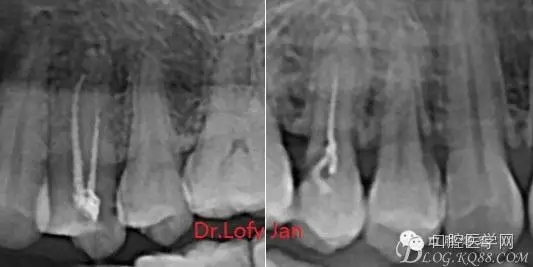

前言:自己做的一些曲面斷層片在未試尖根管治療中的病例整理,發(fā)現(xiàn)問題很多包括自身的,技術(shù)的,還有設(shè)備的問題,予以總結(jié)整理并期待進(jìn)一步提高。

病例分析:曲面斷層片在x線輔助診斷與檢查中目前大多數(shù)文獻(xiàn)和著作都建議只能作為初診拍片檢查手段,不能作為終末疾病的確診與手術(shù)療效的評價指標(biāo),臨床大部分中小型門診都因為設(shè)備不齊全導(dǎo)致信息偏差很大。